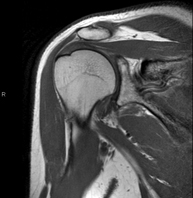

- Shoulder MRI

Examination to study injuries to tendons, muscles and joints. Its main use is to diagnose injuries to the rotator cuff tendons. It lasts approximately 20 minutes. It is a radiation-free procedure.

- Shoulder MRI arthrography

Examination to study injuries to small anatomical structures of the joint that are commonly injured in patients suffering from dislocation or chronic instability. Prior to the examination, a contrast fluid is injected into the joint, guided by X-ray imaging. The total duration of the two procedures is 50 minutes.